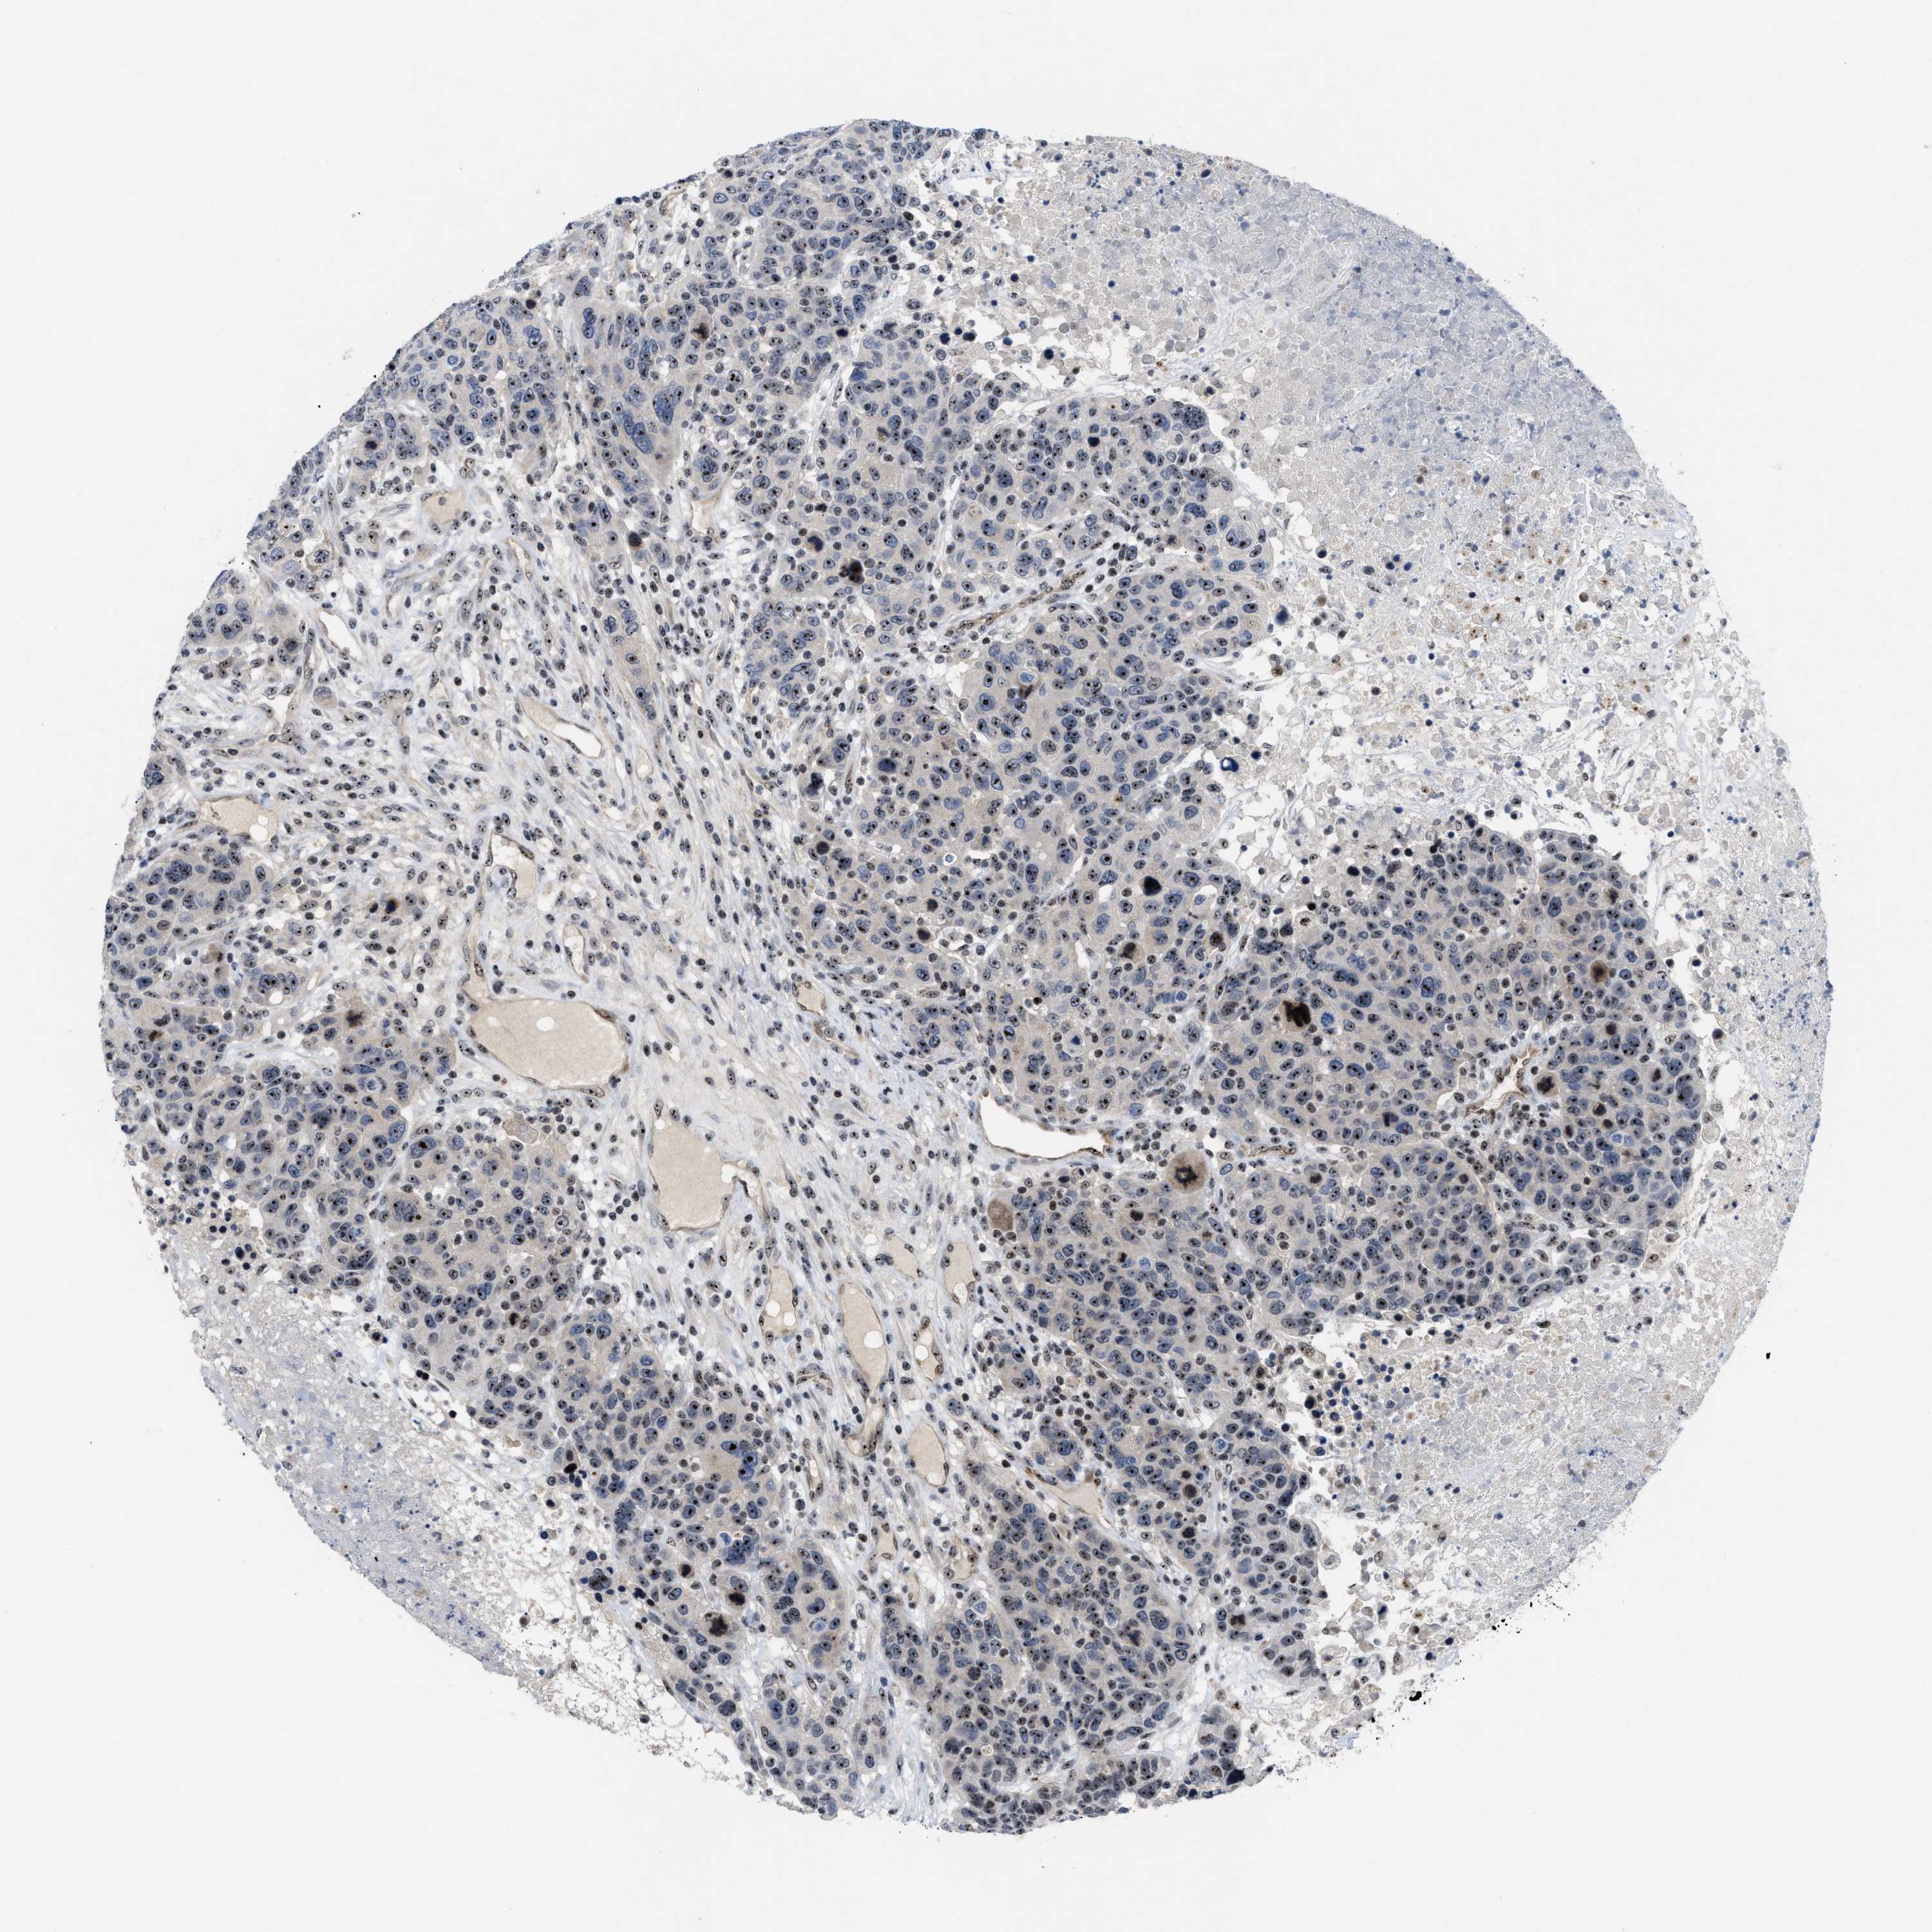

CANCER BREAST CANCER Show tissue menu

BRCA TCGA BRCA VALIDATION PROTEIN EXPRESSION